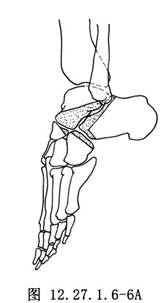

少数病儿残留严重僵硬的马蹄畸形,可采用Lambrinudi关节融合术。本法与上法稍有不同。术前将足部在尽量下垂位照侧位X线片,根据照片描图剪纸法计划切除骨质范围,使能达到纠正畸形的目的(图12.27.1.6-6A)。手术显露同上,去除上述三个关节的软骨面,按计划部分切除距骨头颈部,于舟骨下做一骨槽,使距骨前部嵌入槽中。因距骨已处于完全跖屈位,故三关节融合后,足不能再下垂(图12.27.1.6-6B)。